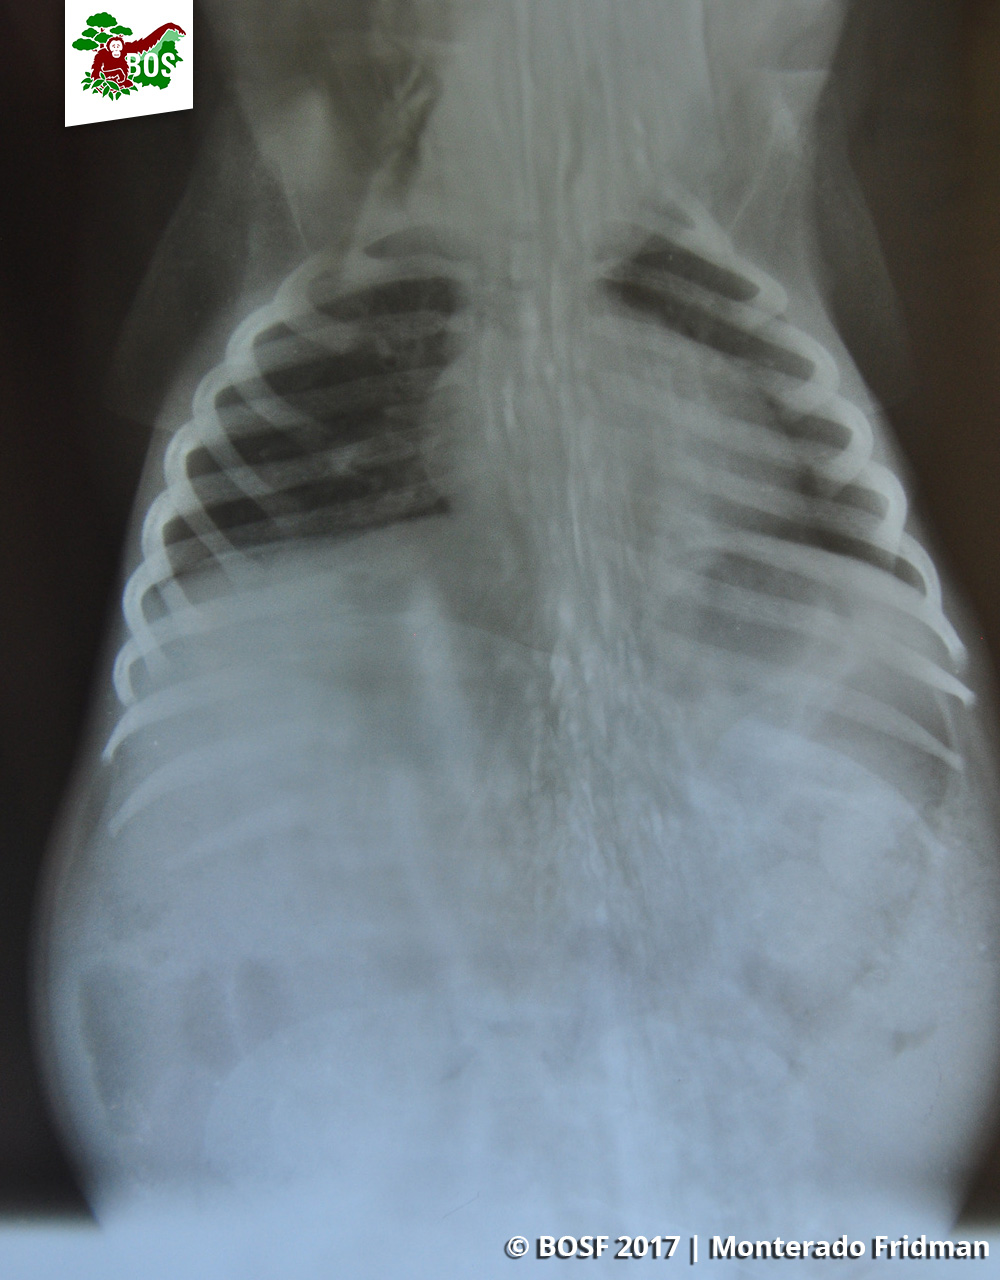

Our vet Lia Kristina, briefly treated Jacqui in Pilang before she was taken to the Nyaru Menteng orangutan rehabilitation centre for a more thorough examination and intensive care. An examination revealed that Jacqui was around 1 year old and weighed 2.6 kilograms, and X-rays showed that fortunately she had no fractures or internal injuries.

Jacqui’s X-ray